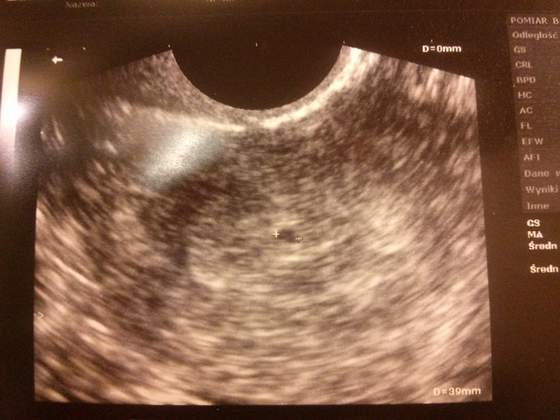

ja po pierwszym usg niecałe 2 tyg temu., kiedy to wiek ciąży był 5 na 6 tydzień. ciąża potwierdzona. teraz następne badanie 14 marca. już nie mogę się doczekać bo wtedy już będzie tętno i uspokoi mnie to za pewnie że wszystko w porządku. objawów jak na razie żadnych oprócz senności.

Dzis bylam na usg widzialam dzidziusia bilo serduszko wymiaryto 8.9 ciaza mlodsza o dwa tygodnie z usg wychodzilo 6 i 5 dz i termin na 23 pazdziernika a z terminu Om 3 styczen i termin na 10 padziernika. W poniedzialek mam wizyte u lekarza

Byłam dziś na 2 wizycie. Wg OM to 9.6. Maleństwo ma 32 mm, usg zmieniło zdanie i ciążą nie jest młodsza o 3 dni, tylko dla odmiany starsza o 3 dni. Ale i błąd pomiaru na tym etapie wynosi prawie tydzień.

Słyszałam serduszko, gin pokazał gdzie lapki, gdzie nóżki i gdzie glowka. Na tym etapie to taka kijanka, że w życiu bym sama nie zgadla. Mózg jest, uff

)))) Dzidziuś mierzy 0,72 cm. Serduszko bije jak szalone, a wiek ciąży zagadza się z terminem OM czyli 6 tydz i 4 dzień

I ja po wizycie. Chyba znowu rośnie mi kurdupelek

, bo 6 tydz 3 dzień, a ono ma 63 mm. Serduszko bije jak dzwon. Wyniki badań rewelacyjne. Co mnie zaskoczyło to lekarz pamiętał mnie z poprzedniej ciąży, to miłe.

moj nerwowy tydzien sie zakonczyl.moj berbec ma 6mm dlugosci i pieknie bijace serducho.nie dal mi lekarz zadnego zdjecia tylko zrobil notatke w karcie ciazy ktora mam zalozona juz od dwuch tygodni. moja ciaza jest o tydzien mlodsza